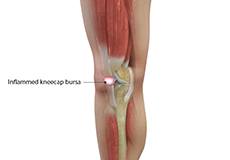

Kneecap Bursitis

Bursitis refers to the inflammation and swelling of the bursa. Inflammation of the bursa in front of the kneecap (patella) is known as kneecap bursitis or prepatellar bursitis.